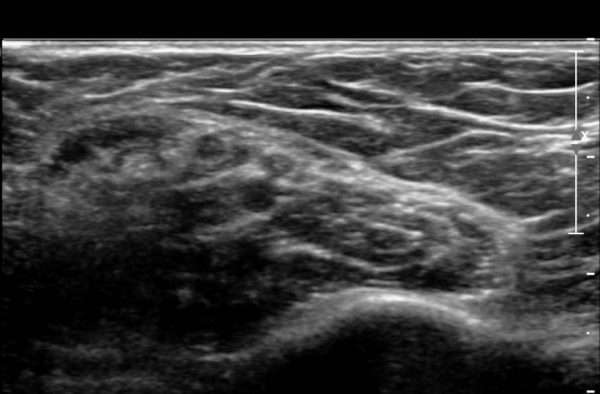

ŽÃËÀÚ¸¦ »ó¹ÚºÎ ¸»´ÜÀ¸·Î  ¿Å°Ü ÆÈ²ÞÄ¡ ºÎÅÍ ±ÙÀ§ºÎ·Î À̵¿ Çϸ鼭 Á¤Á߽Űæ Ⱦ´Ü¸é°Ë»ç¸¦

½ÃÇàÇÏ¿´´Ù(»çÁø 2).  ÆÈ²ÞÄ¡ ÁÖ¸§  ¾à  3cm ±ÙÀ§ºÎ¿¡¼­ Á¤Á߽ŰæÀÇ ÀϺΠ´Ù¹ß(fascicle)ÀÇ Àú¿¡ÄÚ ºÎÁ¾ÀÌ

°üÂûµÈ´Ù(»çÁø 3 , 4,  5,).